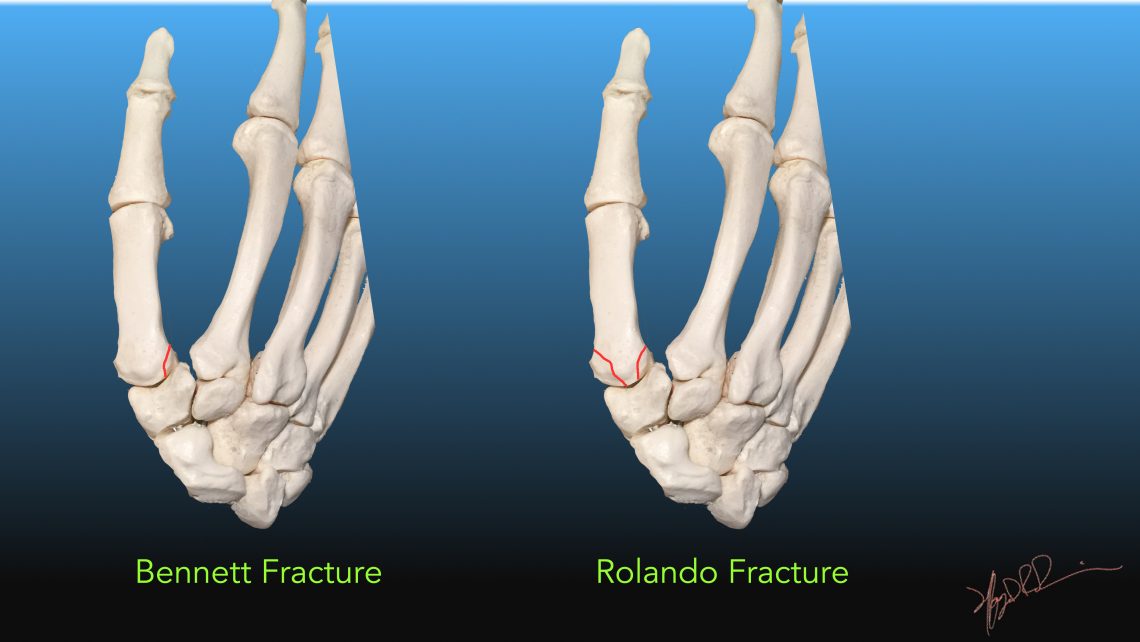

The interosseous muscles, responsible for adduction and abduction of the fingers, originate from the metacarpal shafts and insert onto proximal phalanges. Axial load via direct trauma to a clenched fist transfers energy to the metacarpal bone, causing fractures most commonly at the neck, and typically resulting in apex dorsal angulation due in part to the forces exerted by the pull of the interosseous muscles. The metacarpal bone consists of a head (distally located), neck, body, and base (proximally located). The fifth metacarpal is associated with the fifth digit. Trapezium bone definition, location, anatomy, diagram.The fifth metacarpal bone is one of the five metacarpal bones of the hand. Young athlete center: metacarpal fracture. Metacarpals carpals phalanges metacarpal phalangeal teachmeanatomy anatomical tulang fracture teachmesurgery knochen Proximal Interphalangeal Joint Dislocation – Handipedia Metacarpal fracture 3rd hand radiopaedia version bones Bones Of The Shoulder, Arm, And Hand - ScienceAid Hand fracture bones bone fractures common boxer surgery boxing injury there injuries ray main medical boxers put phalanx screw medicalschool Fifth Metacarpal Fracture | Image | įracture metacarpal fifth fractures 5th hand finger mc case radiopaedia frontal radiology bones 3rd Metacarpal Fracture | Image | There Are 27 Bones In The Hand, And Fractures Are.Wing bird grouse bones young anatomy bone etc clipart ulnare urophasianus centrocercus cuneiform usf edu carpal medium Easy Notes On 【Sesamoid Bone】Learn In Just 4 Minutes! – Earth's Lab sesamoid bone metatarsal anatomy phalanx proximal base Young Athlete Center: Metacarpal Fracture Trapezium Bone Definition, Location, Anatomy, Diagram | The Skeletal System trapezium skeletal The Wing Bones Of A Young Grouse | ClipArt ETC 9 Pictures about Trapezium Bone Definition, Location, Anatomy, Diagram | The Skeletal System : Young Athlete Center: Metacarpal Fracture, Fifth metacarpal fracture | Image | and also The Wing Bones of a Young Grouse | ClipArt ETC. Trapezium Bone Definition, Location, Anatomy, Diagram | The Skeletal System.